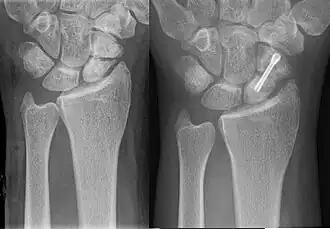

Scaphoid pseudarthrosis, before and after treatment with Herbert screw.

Percutaneous screw fixation is recommended over an open surgical approach when it is possible to achieve acceptable bone alignment closed as minimal incisions can preserves the palmar ligament complex and local vasculature, and help avoid soft tissue complications. This surgery includes screwing the scaphoid bone back together at the most perpendicular angle possible to promote quicker and stronger healing of the bone. Internal fixation can be done dorsally with a percutaneous incision and arthroscopic assistance [17] or via a minimal open dorsal approach,[18] or via a volar approach in which case slight excavation of the edge of the trapezium bone may be necessary to reach the scaphoid as 80% of this bone is covered with articular cartilage, which makes it difficult to gain access to the scaphoid.[19]